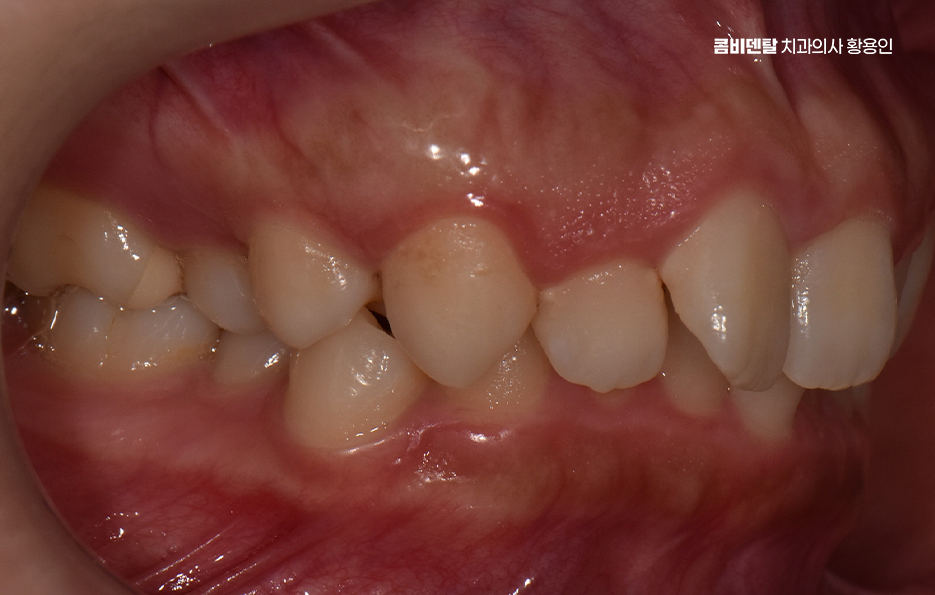

돌출입이라는 표현은 단순히 입이 튀어나와 보인다는 인상만을 의미하지는 않으며 치아가 앞으로 기울어져 있거나, 잇몸뼈 자체가 앞으로 나와 있거나, 입술 두께와 근육 사용 습관까지 복합적으로 작용해 나타나는 경우가 많아서 겉으로 보기에는 비슷한 돌출입처럼 보여도, 실제 교정 계획은 사람마다 크게 달라질 수 있었어요.

비발치 돌출입 교정 가능한 대표적인 케이스는 치아 배열의 공간이 비교적 충분한 경우로서 치아가 전체적으로 가지런하지는 않지만, 심하게 겹쳐 있지 않고 잇몸뼈 안에 어느 정도 여유 공간이 있는 경우에는 발치 없이도 치아를 뒤쪽으로 이동시키는 것이 가능한 경우가 있었어요.

치아 크기가 비교적 작거나, 턱의 크기에 비해 치아가 과도하게 크지 않은 경우도 비발치 돌출입 교정이 가능한 조건 중 하나로 같은 돌출입이라도 치아 크기와 턱뼈 크기의 비율에 따라 치료 접근이 달라지는데 치아가 상대적으로 작은 경우에는 공간을 확보하기가 더 수월하고 이런 경우에는 치아를 재배열하면서 자연스럽게 앞니 위치를 조정할 수 있었어요.

턱뼈의 위치와 형태도 중요한 기준이 되며 잇몸뼈 자체가 과도하게 앞으로 튀어나와 있는 골격성 돌출입의 경우에는 비발치 교정만으로는 한계가 있는 경우가 많은 반면 턱뼈의 위치는 비교적 정상 범위에 있고, 치아 배열로 인해 돌출이 강조되어 보이는 경우라면 비발치 교정이 현실적인 선택지가 될 수 있었어요.